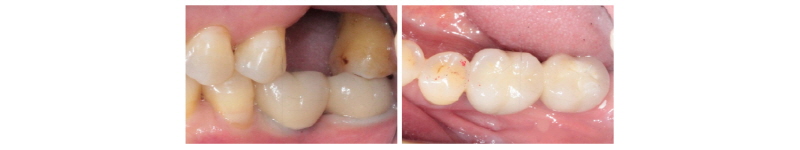

Fig. 30. PFM bridge (final prosthesis) was cemented on #i36, i37. |

Ju Whan Lee : Computer-guided Flapless Implant Surgery and Immediate Loading with Customized Restoration, Comparing and Reviewing Error of Guided Surgery. Implantology 2017 |

본 59세 여환은 양쪽 위, 아래 큰 어금니가 흔들리고 잇몸이 부었으며 왼쪽 아래 큰 어금니는 오랫동안 없었다는 주소로 본원에 내원하여 임상 및 방사선학적 검진 결과 아래와 같이 관찰되었다. #33 치아는 Mob (+++) Per (+)와 bone loss, #16, 26, 46 치아는 Mob (++/+++) Per (+)와 bone loss, #36, 37 치아는 missing 상태였다. 이에 #16, 26, 33, 46 치아는 hopeless teeth, #17, 36, 37, 47 치아는 missing teeth로 진단되었다(Fig. 19). #16, 26, 33, 46 치아는 발치 후, #i16, i17, i26, i33, i36, i37, i46, i47에 implant 식립과 #i16, i17, i26에 sinus lifting 및 #i33, i46, i47에 GBR을 계획하였다. #i36, i37은 flapless implant surgery 및 immediate loading을 계획하였다. #16, 26, 33, 46 치아를 발치하였고, 2개월 후에, 상, 하 rubber impression 채득 후, stone model 제작하였다. 또한 arch 전용 tray를 bite한 상태로(Fig. 20, 21) CBCT 촬영을 하였다(PHT-30LFO, VATECH). 이후 CBCT 영상과 alveolar ridge와 soft tissue model을 scanning한 영상(TRANSFORMER, Megagen)을 정합하였다. 새로운 영상을 바탕으로 #i36, i37 위치에 implant fixture 식립과 customized abutment와 provisional bridge를 design하였다(R2GATETM, Megagen, Fig. 22, 23). Design대로 3D printer (Perfactory Digital Dental Printer 3, EnvisionTEC) 통해 surgical guide를 제작하였고(Fig. 24) milling machine (TicamPro and WhitecamPro, Megagen)으로 customized abutment와 provisional bridge를 milling하였다(Fig. 28). 임플란트 수술은 5회에 걸쳐서 진행하기로 하였다. 첫 번째 수술일에는 #i36, i37 fixture 식립과 동시에 abutment 체결과 provisional bridge를 합착하였다(Fig. 25-27, 29). 이후, 1개월 후에 #i16, i17 fixture 식립과 lateral approach로써 sinus lifting을 시술하였다. 3개월 후에 #i36, i37에 최종 인상 채득하여 도재금관 수복을 하였다(Fig. 30, 31). 향후 남은 부위에 임플란트 수술 및 보철 진행 예정이다.